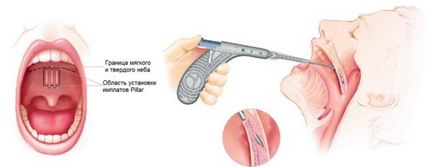

A különböző mellbimbó. és kondenzátor beilleszti hasznos az égen gyenge szövetek hajlamosak a megszűnése. Szúr emelje fel őket, és tartani egy bizonyos helyzetben, bővíti a teret a szabad légzést.

Erősíti az izmokat az ég, figyelmeztető megszűnése alvás közben. A készülék jellemzője a magas hatásfok, a betét el lehet távolítani, ha szükséges.

Alkalmas betegek obstruktív alvási apnoe mérsékelten súlyos. Az implantátum ellenjavallt elhízás és veleszületett deformitások az ég.